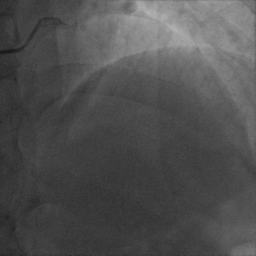

3.择5F冠脉公用导管多体位头照

结果:

右冠优势型冠脉,LM(-),LAD近段粗大,内膜不光滑

D1开口后管状狭窄,狭窄最重90%,D1开口狭窄40-50%,前向血流TIMI Ⅲ级

LCX内膜不光滑,前向血流TIMI Ⅲ级

RCA内膜不光滑,前向血流TIMI Ⅲ级

造影结果显示:对角支发出后狭窄90%,狭窄前后血管直径相差大